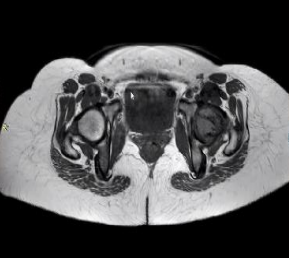

31 year old female presented to us with complaints of limp while walking from past few months. No history of fever, loss of appetite, weight loss or any other constitutional symptoms. Patient is a post operated case of Medulloblastoma brain and occipital craniotomy with VP shunting was done in May 2018 in London for the same along with adjuvant chemo-radiation. Patient received craniospinal radiotherapy (35Gy/21fractions) + (20Gy/12 fractions) for approx. 6 weeks in Aug-Sep 2018. Patient received 6 cycles of Cisplatin, Vincristine and Lomustine, during Sep 2018-Dec 2018. Patient was on regular follow up and regular MRI Brain was done during follow up and patient was asymptomatic during the time period of last 4 years, until last month when she developed sudden onset right lower limb limp while walking. Patient was evaluated for above mentioned complaints and relevant scans were done. On X ray (Fig. 1),   MRI (Fig. 2) and PET scan (Fig. 3) multiple lytic lesion were seen involving D7 vertebra, right ischium and left proximal femur. Left proximal femur lesion was measuring 5.5 x 3.8 x 3.2 cm with a cortical breach. CT guided biopsy from D7 vertebra was done which showed typical emperipolesis (Fig. 4) S/O Rosai Dorfman Disease. IHC was done and was positive for S100 and CD68 suggestive and negative for CD1a suggestive of Rosai Dorfman Disease. High risk of pathological fracture of left proximal femur (Mirel’s Score – 11) was explained to the patient and cemented bipolar hemiarthroplasty was done for left hip. Post op patient was mobilized on Day 1 and dressing was changed at Day 5 and patient was discharged at Day 6. Final histopathology impression was s/o Extranodal Rosai Dorfman disease.

Fig. 2 (a) MRI Coronal section                   (b) Axial Section